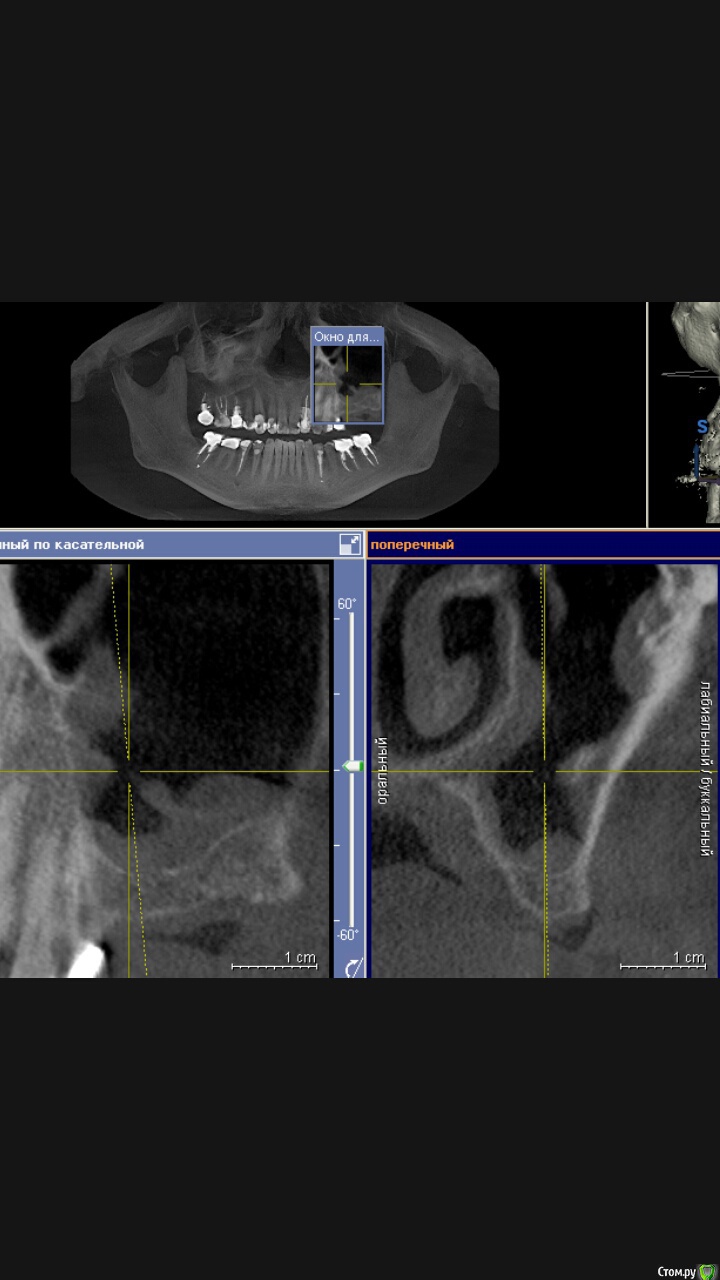

Доктор Добрых Дел Опубликовано 7 сентября, 2015 Поделиться Опубликовано 7 сентября, 2015 (изменено) У пациента была обнаружена киста в пазухе, направлен к ЛОРу. Киста удалена. Прошло полтора месяца. На КТ выглядит пазуха вот так:Вопрос - стоит ли сейчас делать синус лифтинг или нужно ещё подождать?И какие вообще мнения относительно проведения синус лифтинга при наличии подобных изменений в пазухе. Изменено 7 сентября, 2015 пользователем Доктор Добрых Дел Ссылка на комментарий

major Опубликовано 7 сентября, 2015 Поделиться Опубликовано 7 сентября, 2015 У пациента была обнаружена киста в пазухе, направлен к ЛОРу. Киста удалена. Прошло полтора месяца. На КТ выглядит пазуха вот так:Вопрос- стоит ли делать синус лифтинг или ещё подождать?И какие вообще мнения на счёт проведения синус лифтинга при наличии подобных изменений.Screenshot_2015-09-07-12-44-29.jpegСами лоры просят 4 месяца не трогать, после таких операций пристеночное утолщение до 5-7мм через 4 мес. считают приемлимым для синус-лифтинга Ссылка на комментарий

Доктор Добрых Дел Опубликовано 7 сентября, 2015 Автор Поделиться Опубликовано 7 сентября, 2015 Сами лоры просят 4 месяца не трогать, после таких операций пристеночное утолщение до 5-7мм через 4 мес. считают приемлимым для синус-лифтингаСпасибо Ссылка на комментарий